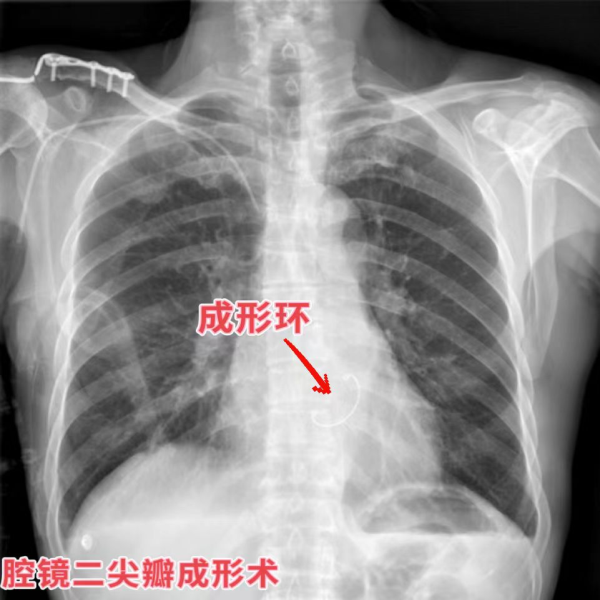

再说开篇时说的两位大爷,俩人在同一手术日先后接受了“小切口主动脉瓣置换术”和“胸腔镜二尖瓣成形术”。微小的切口缩短了手术时间,减少了手术创伤,使二老术后恢复迅速,很快回到了普通病房,术后恢复较快,很快康复出院。患者和家属对手术效果都非常的满意。

术后胸片(与常规正中切口对比):